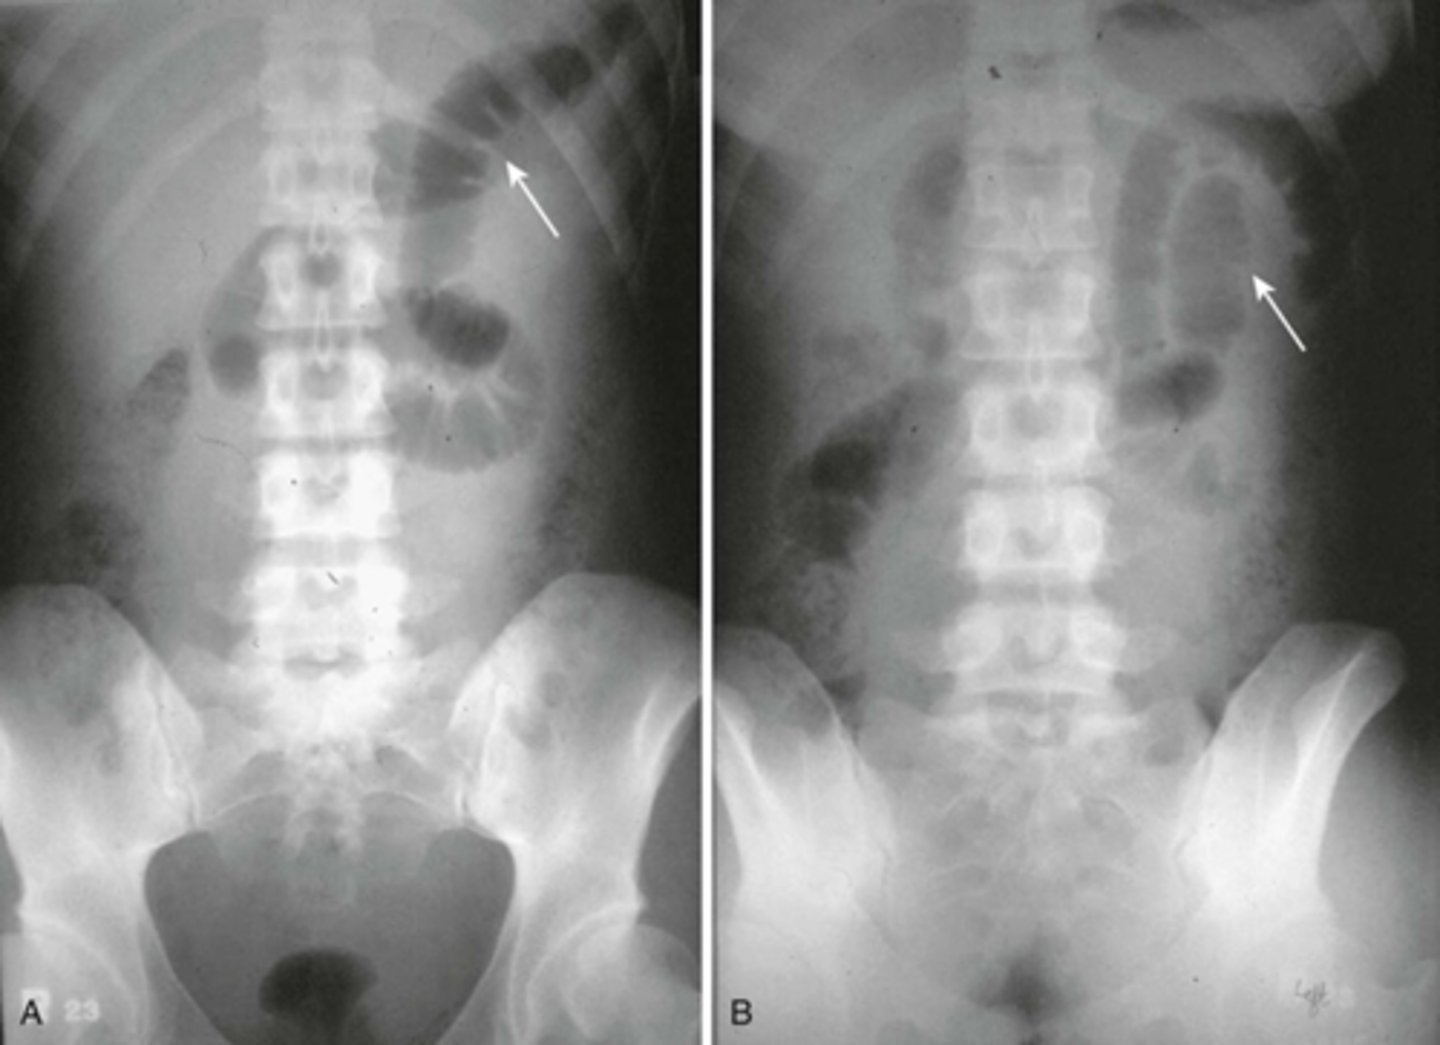

Normal prone abdomen

BLACK ARROW: S-shaped rectosigmoid colon.

WHITE ARROWS: air throughout the remainder of colon

In prone position, ascending, descending and rectosigmoid colon are the highest parts of the large bowl and will fill with air.

Normal colonic distension from barium study.

WHITE ARROW: normal distension of colon